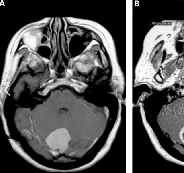

岩斜区脑膜瘤什么时候需要手术?岩斜区脑膜瘤是较具挑战性的病理之一,因为其位置深,与重要的神经血管结构关系密切。患者可能没有症状,或者受到颅内压升高、脑神经、小脑或...

岩斜脑膜瘤起源于在上颅骨的三分之二中部至五颅神经内侧的岩腹结合处,其中大型岩坡脑膜瘤定义为大小超过3厘米...

枕骨大孔脑膜瘤(FMM)继续挑战神经外科医生,因为这些病变与不能牺牲或缩回的神经和血管结构密切接触。尽管显微外科手术和颅底外科手术有了很大的发展,但FMM的治疗仍然引起了关...